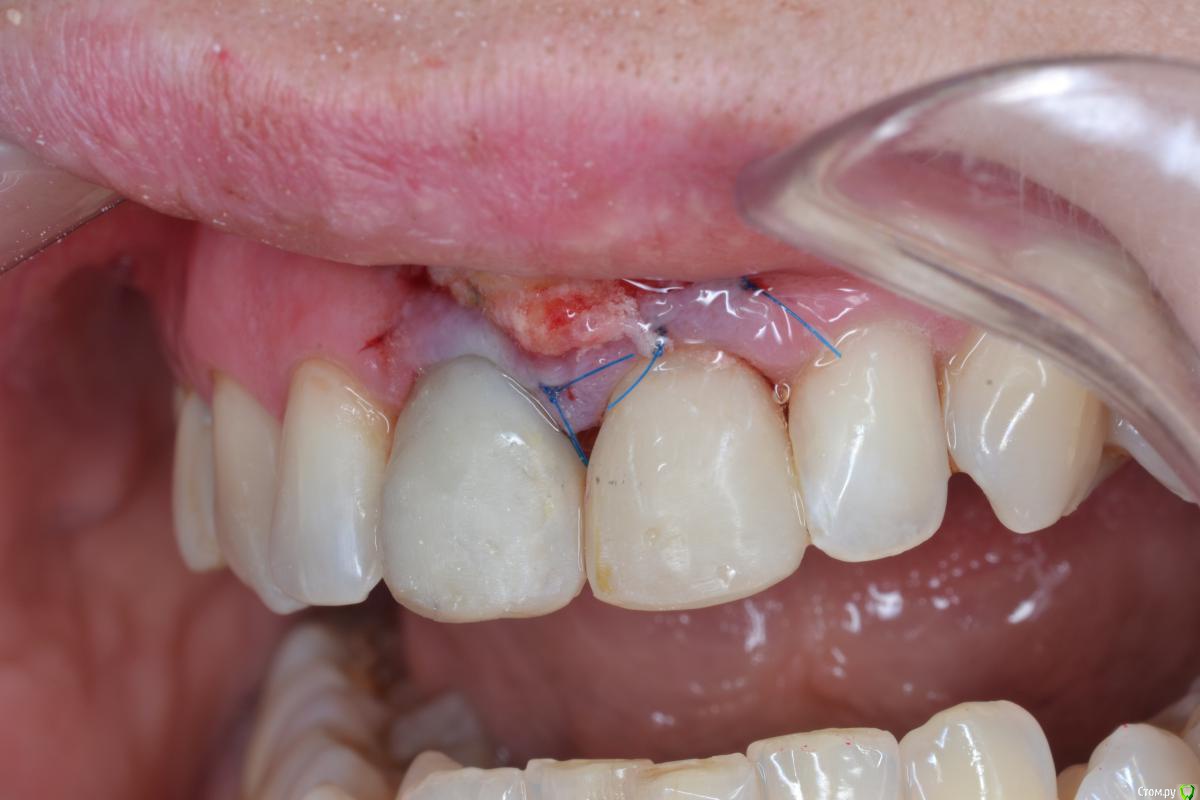

Александр07 Опубликовано 26 июня, 2020 Автор Поделиться Опубликовано 26 июня, 2020 Коллеги, скидываю фото проделанной работы, прошло около 1.5 мес, есть результат, спасибо за помощь, если какие то замечания /советы есть пишите 4 Ссылка на комментарий

колесников Опубликовано 26 июня, 2020 Поделиться Опубликовано 26 июня, 2020 (изменено) Здравствуйте! Не видел этого поста раньше,бегло посмотрел. Определенно проблема была в выборе высоты абатмент и объёме реставрации. Вы убрали композит максимально в основании-это хорошо,но абатмент оставили прежний. Следовало взять новый с высотой уступа 4-5 мм. Край коронки пришеечный следует опустить ниже,иначе десна опять отскочит. И переход слелайте на плавный а под углом,так называемый балкон. Потом будет что отдавить. По Масана сосочек сделали это хорошо и правильно,но с такой реставрацией опасно,мало место лоскуту. К счастью кажется все живы. На данном этапе рекомендую пропилить балкон и этим ограничится. Изменено 26 июня, 2020 пользователем колесников Ссылка на комментарий

Александр07 Опубликовано 27 июня, 2020 Автор Поделиться Опубликовано 27 июня, 2020 Справились одним трансплантом в итоге?)Два, один под сосочек с бугра второй вестибулярно с неба Сст 1 Ссылка на комментарий